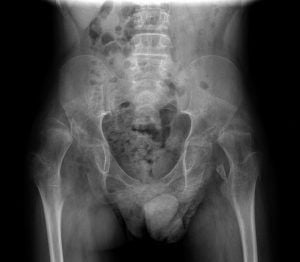

Nei casi di lussazione inveterata dell’anca, il team del Prof. Portinaro esegue anche protesi d’anca con accesso anteriore su pazienti di ogni età grazie all’innovativa tecnica mini invasiva AMIS (Anterior Mini Invasive Surgery). Si tratta di Protesi Anca di Ultima Generazione, un intervento sicuro, rapido (35 minuti) e con recupero veloce (dopo soli 3 giorni, si può tornare a casa autonomamente, senza bisogno di trasfusioni o drenaggi).

- Guided Growth of the Proximal Femur for the Management of Hip Dysplasia in Children With Cerebral Palsy.

- Can we prevent hip dislocation in children with cerebral palsy? Effects of postural management

- D.D.S.H.: developmental dysplasia of the spastic hip: strategies of management in cerebral palsy. A new suggestive algorithm.

- Bilateral hip surgery in severe cerebral palsy a preliminary review.